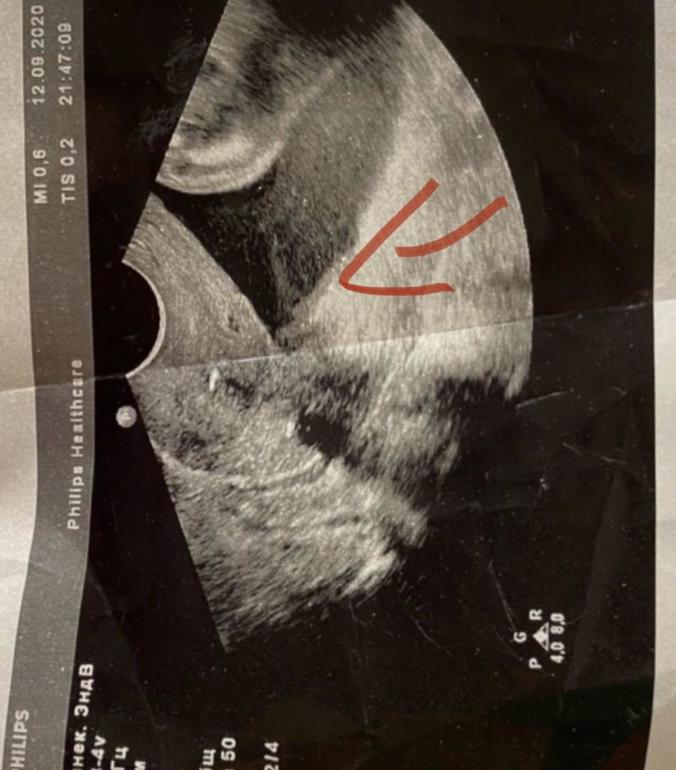

девочки, сегодня опять было узи. внтренний зев воронкообразный, чуть приоткрыт (сколько не сказали) и там внизу, где эта воронка, сказали есть как типа чешуя или шелуха, как осадок какой-то. спросили принимаю ли антибы. ответила да, сказали продолжать курс приема, вот потому что вот эта фигня в виде взвеси есть..

вот где 1-там воронка я если я правильно поняла узиста, то она имела ввиду что там внизу как осадок или взвесь..

Вижу швы.

А то что взвесь в околоплрдных водах- это нормально. Она у всех есть. Это эпителий.

Лили, я совсем маленький кусочек видела на твоём УЗИ. То что плавают точки и кусочки это нормально. Просто необычно что одна часть почти без кусочков а в другой они столпились. Но ты лежала долго и ребенок спал. Потому осело неверно - закон земного притяжения никто не отменял.

Может угол такой. Мне сложно - я свое узи в динамике видела. А тут только 1 фото